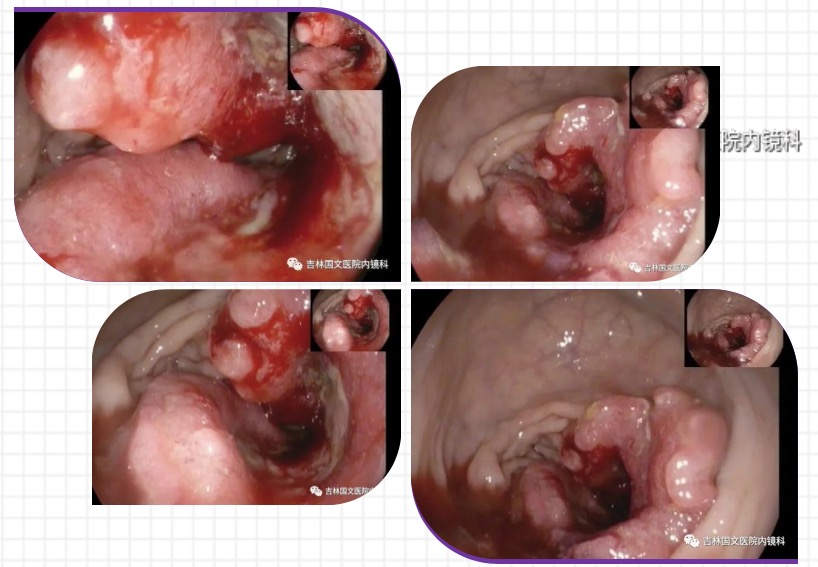

最近就有這樣一起案例,便血后自我診斷為痔瘡,當(dāng)做痔瘡治療了一年多,從未到醫(yī)院詳細(xì)檢查過,近日便血加重,腸鏡檢查后,明確診斷為腸癌,被自己的無(wú)知和自以為是給害了。

借此案例,呼吁大家有癥狀一定要到正規(guī)醫(yī)院規(guī)范治療,以免延誤病情,悔恨終生!將傷害降至最低,將癌癥的種子扼殺在搖籃里。

以為是痔瘡 其實(shí)是腸癌